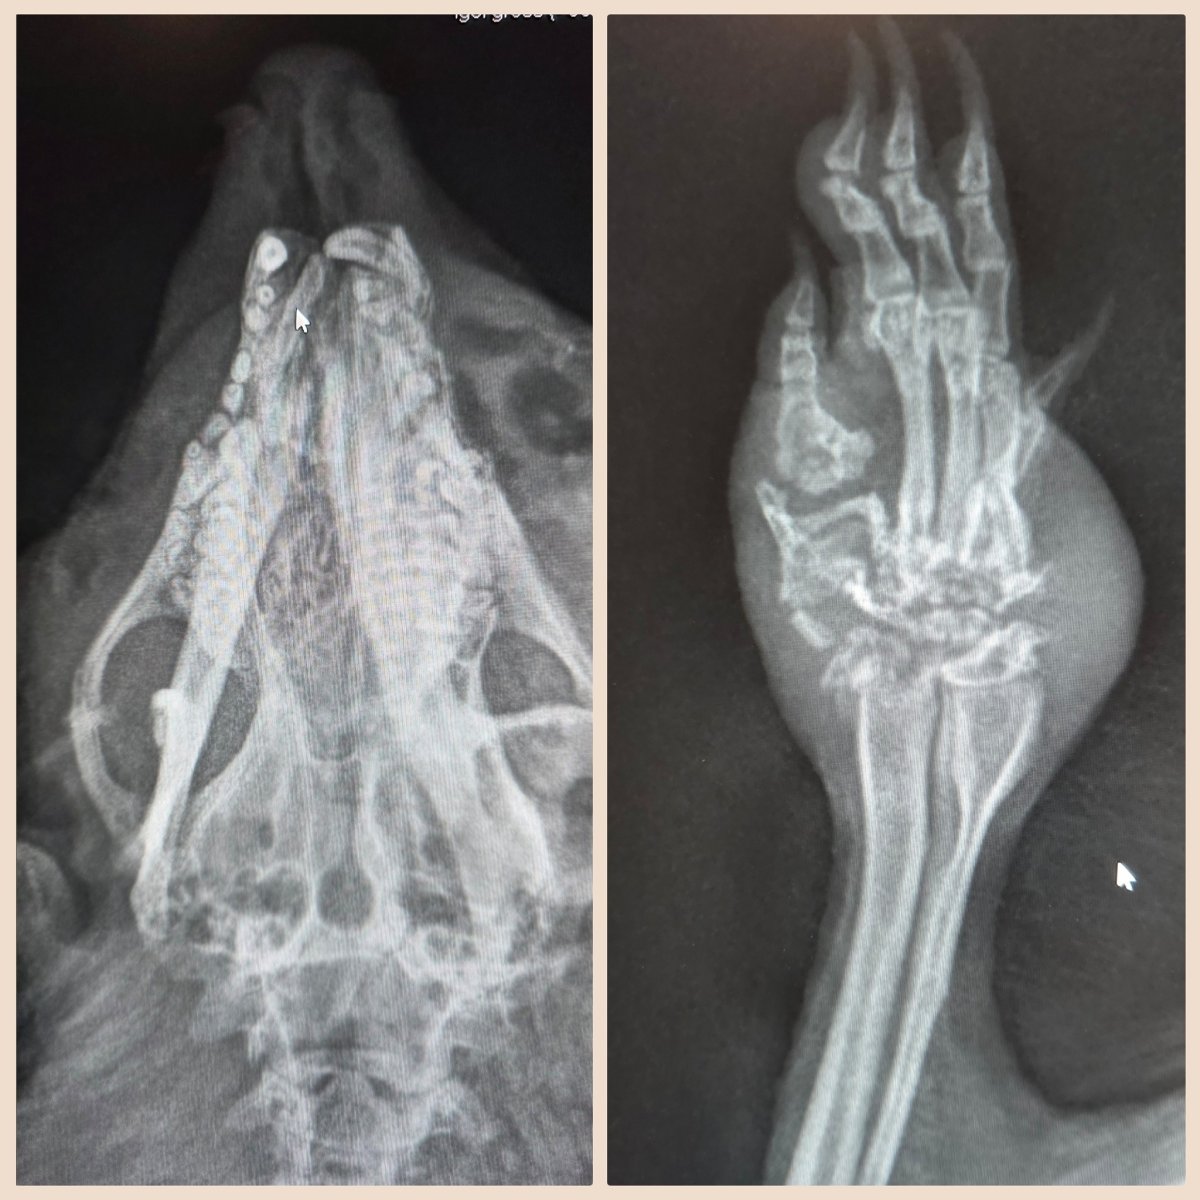

Die Röntgenbilder zeigten dann das ganze Ausmass seiner Verletzungen .

Der Unterkiefer war gebrochen und es hat sich auch da schon Eiter angesammelt. Auch beim Vorderbeinchen war eine ältere Fraktur zu erkennen. Leider hat sich der Knochen schon angefangen aufzulösen und die Schwellung entstand durch entzündetes Gewebe.